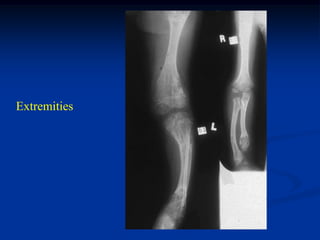

Case #568

3 year male with multiple enchondromatosis

Extremities